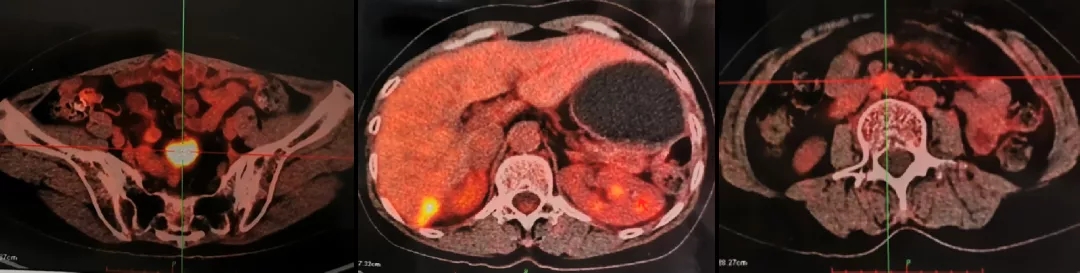

2016.10.14查PET-CT: 盆腔内软组织密度灶,FDG代谢异常增高,考虑转移灶;右肝后下段包膜处结节样、片状转移灶;左肾前方斑片状,腹主动脉管壁处(L3椎体水平)FDG代谢轻度增高,考虑肿瘤活性组织存在。

PET-CT检查结果

2021.4.23复查CA125上升至70.2U/ml。2021.4.24 CT:肝肾隐窝病灶增大,考虑复发。患者退出BGB-290临床试验。

2021.5.8 PET-CT:肝肾隐窝转移灶。2021.5.12复查CA125水平为95.5U/ml。